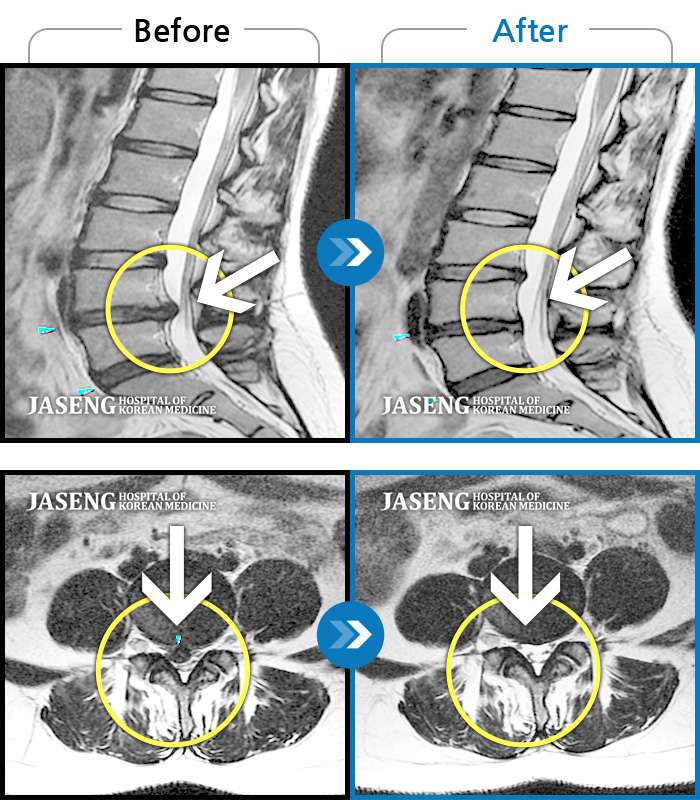

허리디스크

보라매 · 왕오호 원장

허리와 좌측 엉치 통증

촬영시기

2015.12.29 ~ 2018.10.11

2018.12.28

조회수 3,313